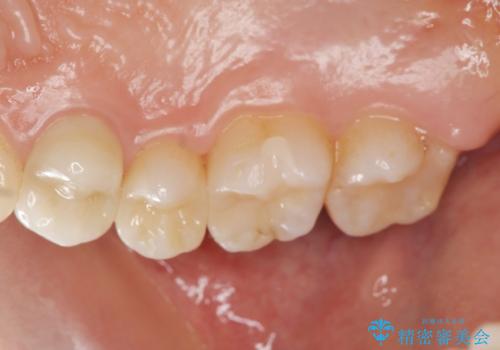

銀歯を白くしたい 隙間がしみる

- 前に詰めた銀歯のところがしみる、白くしたいと希望され来院されました。

銀歯・虫歯を丁寧に除去し、残存歯質にピッタリと合ったセラミック修復を計画します。